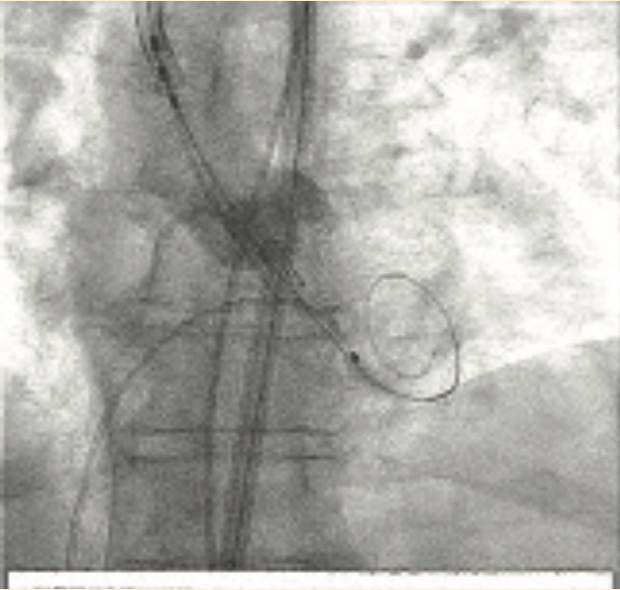

We planned to use cerebral protection during the case upfront, but the patient was known to have anomalous origin of her bilateral carotid arteries off of a single branch from the aortic arch, separate from the right brachiocephalic, and an anomalous insertion of the brachicephalic to the distal arch (Figure 2). We performed an aortic arch angiogram using a 15 cc contrast injection through a 5 French (Fr) pigtail with the ACIST CVi system (ACIST Medical) (Figure 3, Video 1) to guide the cerebral protection device from the anomalous brachiocephalic to protect the carotids. We proceeded with laceration of the left coronary cusp aortic valve leaflet. Aortic root angiography was performed using the same 5 Fr pigtail and a 10 cc contrast injection (Figure 4), then coronary angiography to identify the left coronary cusp (Figure 5). The optimal alignment of the left coronary cusp was determined by using a 6 Fr Amplatz left (AL) 1 guide catheter and a 6 cc injection with a lower pressure injection (Figure 6, Video 2). Finally, after the laceration was completed and the valve deployed (using small test injections from the ACIST contrast injector) (Figure 7, Video 3), we performed peripheral angiography with the 5 Fr pigtail advanced from the contralateral iliac artery to ensure adequate hemostasis of the large 14 Fr sheath access site (Figure 8, Video 4).